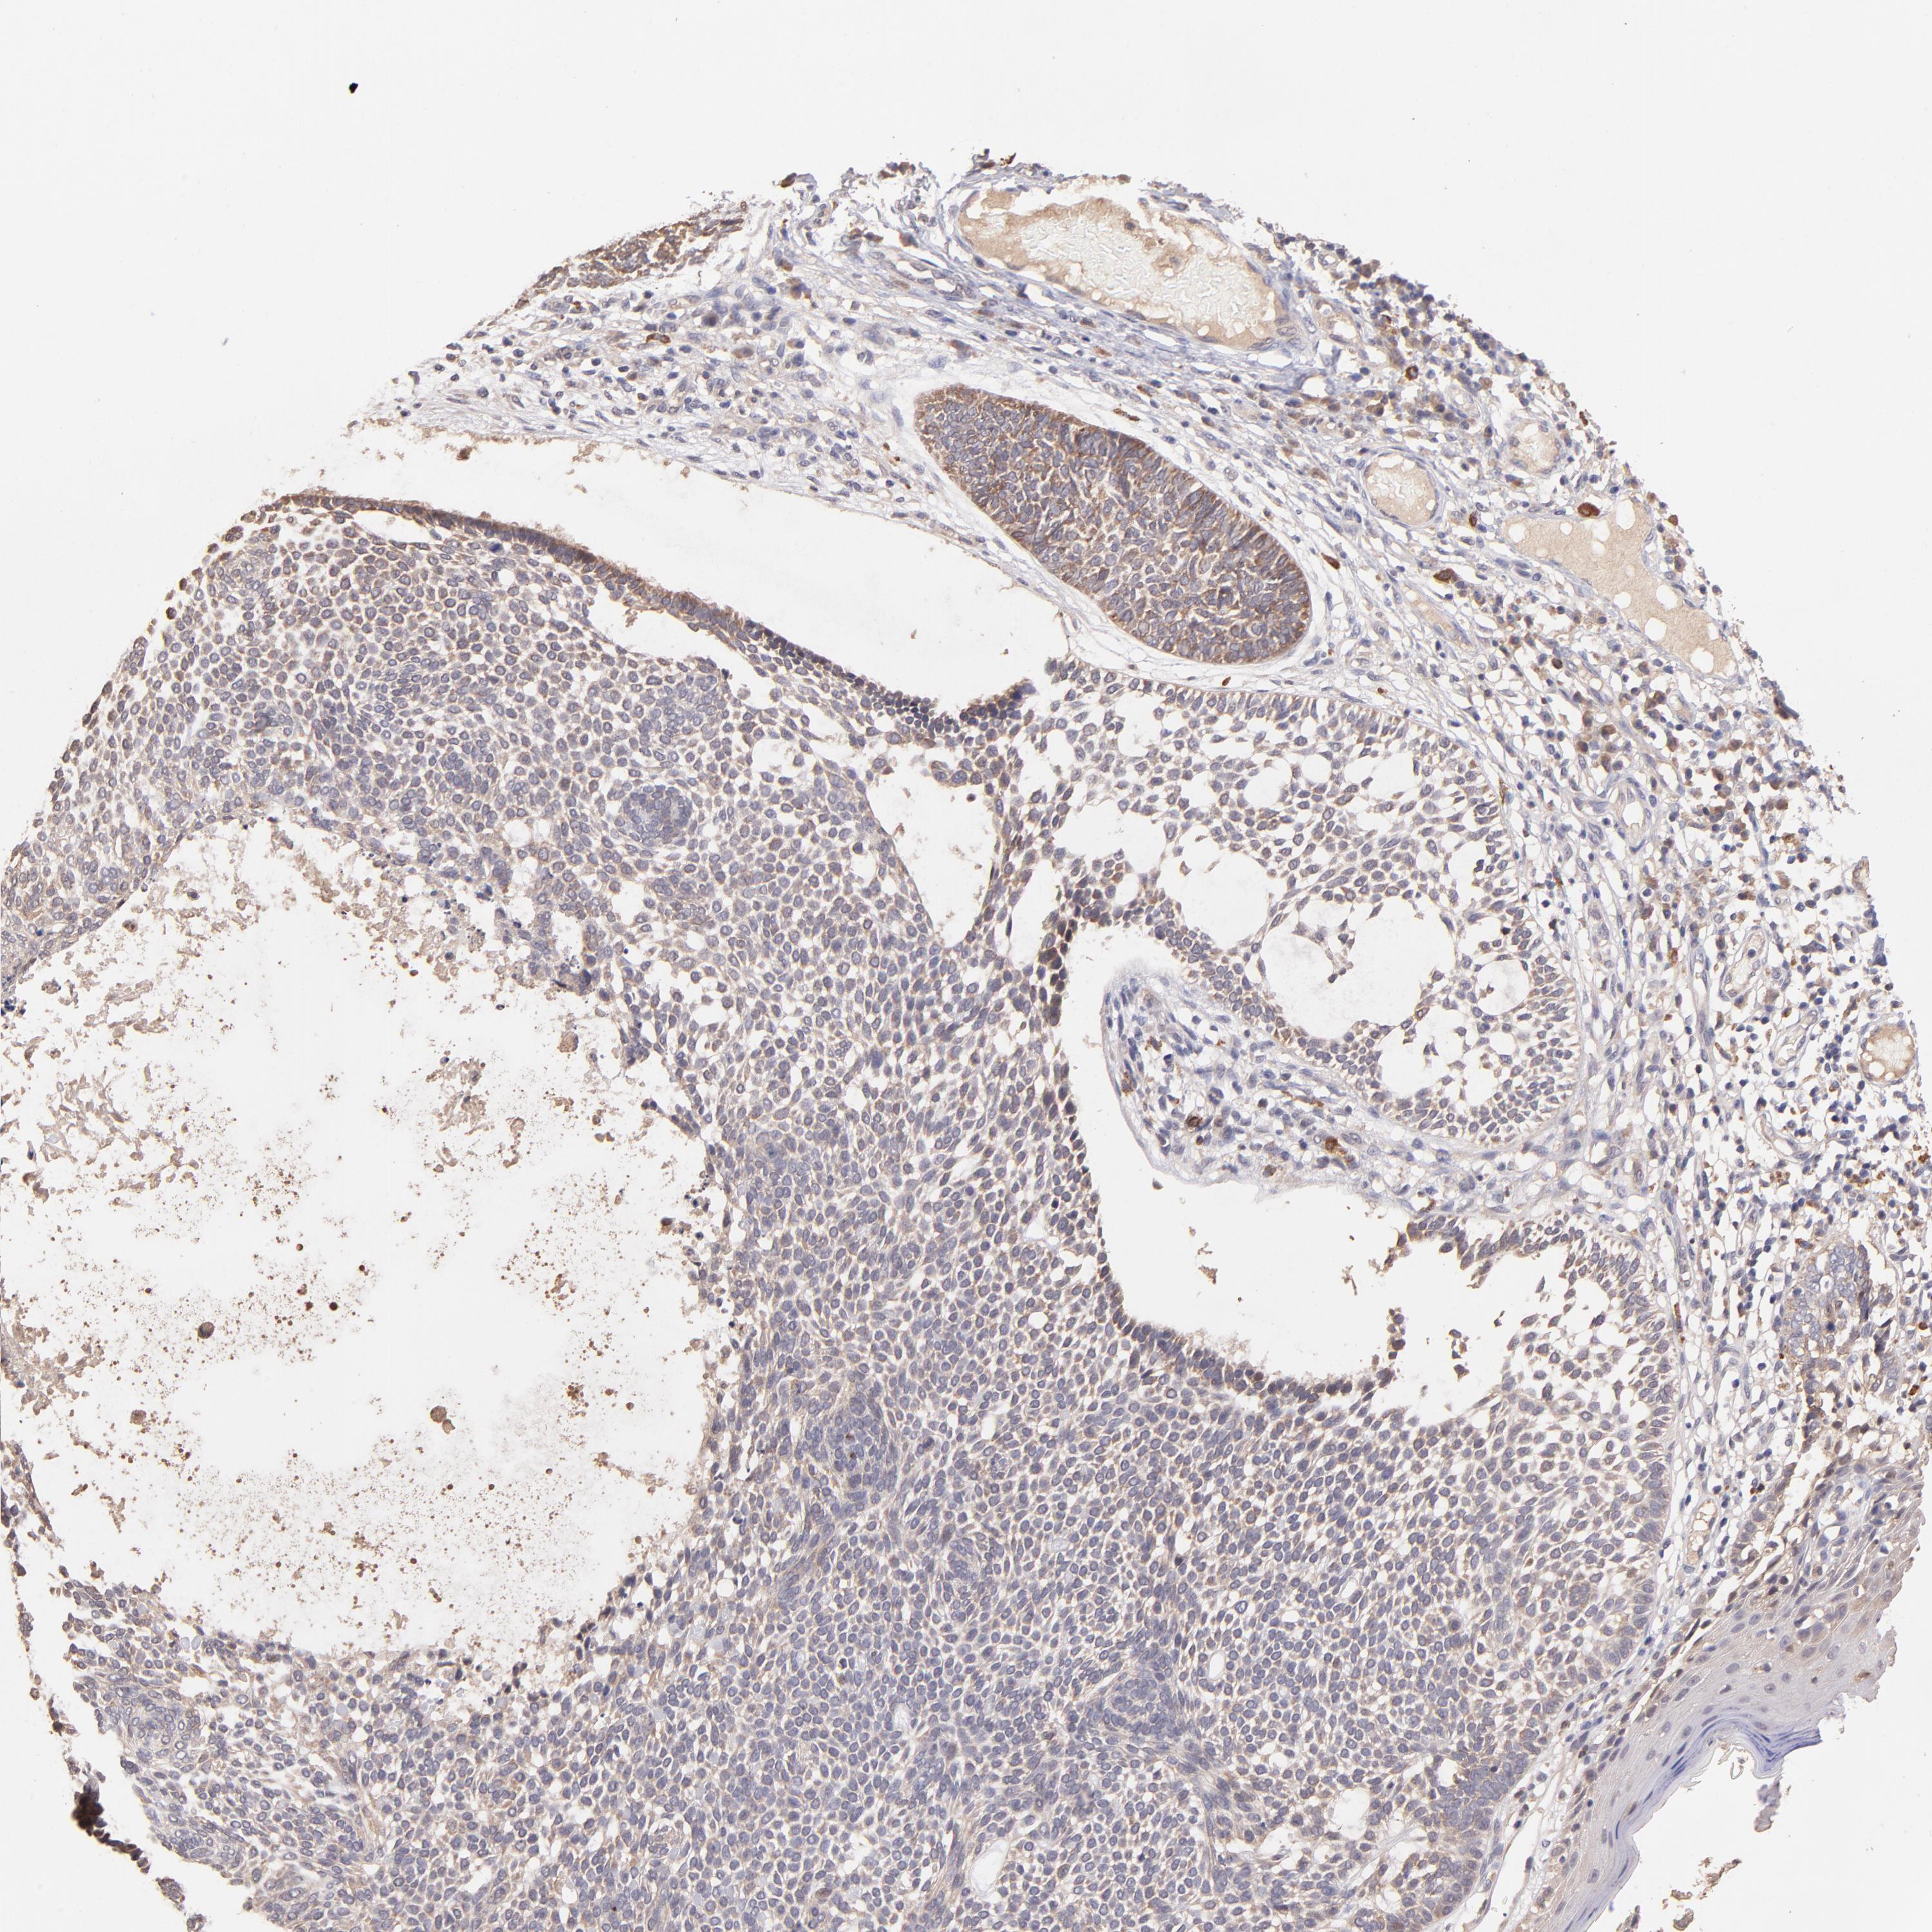

CANCER SKIN CANCER Show tissue menu

Basal cell and squamous cell cancer

SKIN CANCER - Protein expressioni

A mouse-over function shows sample information and annotation data. Click on an image to view it in a full screen mode. Samples can be filtered based on level of antibody staining by selecting one or several of the following categories: high, medium, low and not detected. The assay and annotation is described here.

Each image is clickable and will lead to virtual microscopy that enables deeper exploration of all samples and also displays staining intensity scores, fraction scores and subcellular localization as well as patient and tissue information for each sample.

Antibody HPA002633

Squamous cell carcinoma, NOS

Basal cell carcinoma